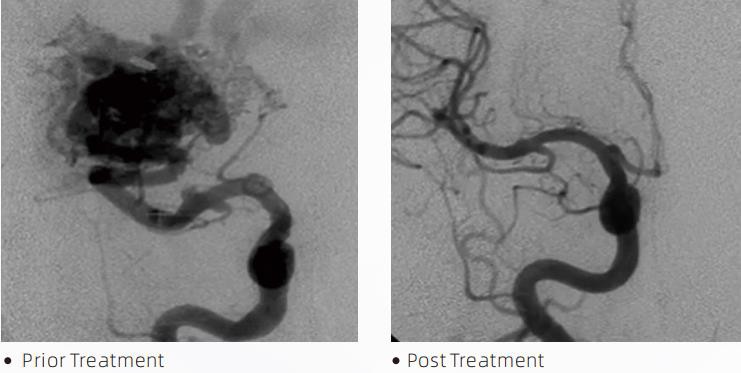

LavaTMšķidrā emboliskā ierīce ir embolijas līdzeklis, ko izmanto neirointervencijās, lai bloķētu mazus smadzeņu asinsvadus. Atšķirībā no citiem embolijas līdzekļiem, kas ir iepriekš sagatavoti vai gatavi lietošanai, tas ir šķidrums, ko caur mikrokatetru var ievadīt asinsvadā, kas ir jānoslēdz. Kad tas ir traukā, tas sacietē un aizsprosto trauku, radot pastāvīgu aizsprostojumu. Tas ir izgatavots no bioloģiski saderīga materiāla, kas palīdz izvairīties no nevēlamām blakusparādībām pacientam. Turklāt, tā kā tam nav nepieciešama iepriekš izveidota forma. To var veidot un pielāgot ārstējamā bojājuma izmēram un formai, radot labāku precizitāti un aizpildot sarežģītākas asinsvadu telpas. Lavas šķidrā emboliskā ierīce ir pieejama 12, 18 un 34 formātā. Zemākas viskozitātes formulai (Lava 12) ir vēlama, ja mikrokatetru nevar virzīt tuvāk bojājuma vietai un mērķa zona joprojām atrodas pārāk tālu no mikrokatetra gala. Zemāka viskozitāte un lēnāks kopolimerizācijas laiks ļauj šķidrajam embolijas līdzeklim plūst dziļāk, sasniedzot vairāk distālos bojājuma apgabalus.

4. Lava ir ļoti efektīva grūti sasniedzamu smadzeņu zonu ārstēšanā, sniedzot izcilus rezultātus mūsu pacientiem.